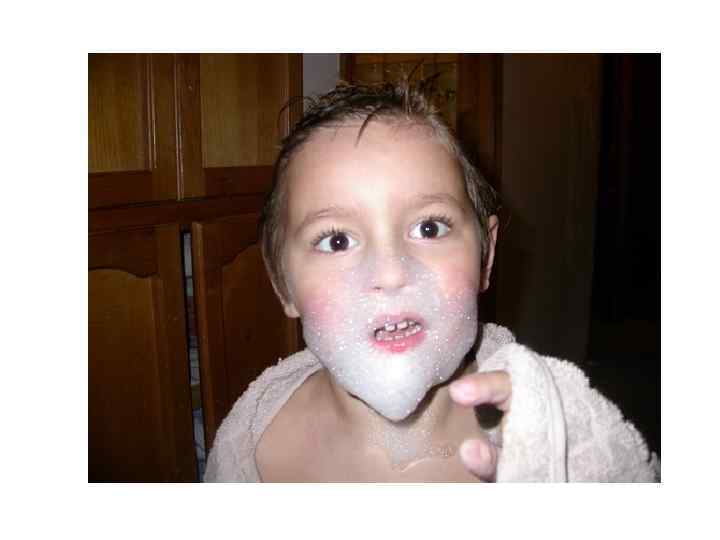

• Аэрофобия, акустофобия, фотофобия провоцирование пароксизмов даже лёгким движением воздуха, шумом, ярким светом. Пароксизмы длятся несколько секунд и сопровождаются мучительными судорогами лицевых мышц, выражением ужаса на лице, расширением зрачков. Больной с криком откидывает голову назад, его руки дрожат. Дыхание учащается, становится свистящим, неровным, с глубокими шумными вдохами; возникает чувство стеснения в груди, в акт дыхания вовлекаются мышцы плечевого пояса. Больной возбуждён, агрессивен, кричит и мечется в отчаянии, может ударить, укусить или плюнуть на окружающих. Из-за сильного слюнотечения он постоянно сплёвывает.

• Приступы возбуждения во второй период болезни учащаются, следуют друг за другом. Больной худеет, отмечают повышенное потоотделение. Развиваются слуховые, зрительные и обонятельные галлюцинации. Сознание, как правило, сохранено и становится спутанным лишь к концу заболевания. Второй период болезни длится 2 -3 дня, редко до 6 сут.